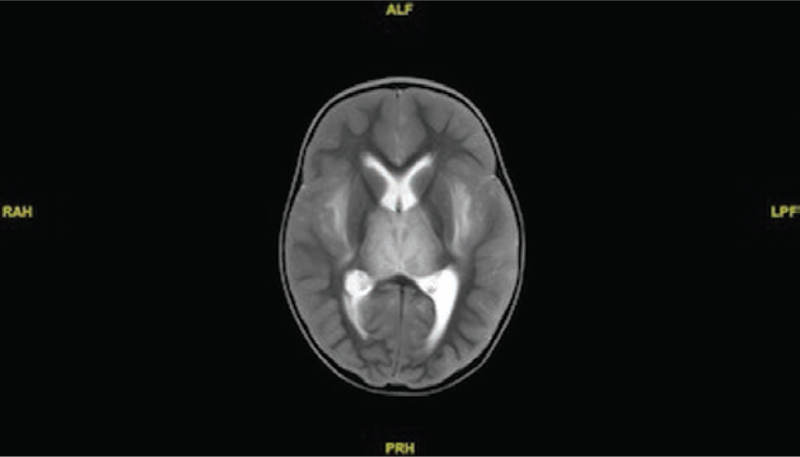

On illness day 8, the patient was transferred to the emergency department of hospital B, where he was noted to have a Glasgow Coma Scale score of 7; he was placed on invasive mechanical ventilation. Radiography of his chest revealed bilateral infiltrates. A head CT scan revealed bilateral decreased attenuation involving the capsule area. Later that day, he was transferred to the PICU of hospital C, where a neurological examination revealed intact pupillary light and gag reflex. Inotropic support was required for his bradycardia and occasional hypotension. He was started on IV vancomycin, IV ceftriaxone, and oral oseltamivir. His hepatic transaminase levels and results of his coagulation studies were all within their reference range (Table 1). His initial white blood cell count was 7500/μL with 70% neutrophils and 22% lymphocytes. A repeat head CT scan performed after his admission to hospital C revealed symmetric areas of decreased attenuation in the external capsules and inferior temporal lobes bilaterally, with partial effacement of the cortical sulci. Electroencephalography revealed bilateral parietal spike activity. A nasopharyngeal swab tested positive for influenza A(H1N1)pdm09 viral RNA in a multiplex respiratory pathogen panel (BioFire Diagnostics, Salt Lake City, Utah). Results of brain MRI performed on illness day 9 were significant for bilaterally symmetric restricted diffusion and extensive diffuse signal abnormalities along the external capsules, medial temporal lobes, and pons, consistent with ischemia/infarction (Figure 1). Levetiracetam was continued for the necrotizing encephalitis diagnosis. Oral oseltamivir was discontinued, and IV peramivir was started. Antibiotics were discontinued, and he received 1 dose of IV immunoglobulin (1 g/kg) and was started on methylprednisolone (30 mg/kg per day); after 4 days, he was switched to prednisolone (2 mg/kg per day) for an additional 3 days. The results of bacterial cultures of blood, urine, and tracheal aspirate specimens obtained on admission were negative.

Figure 1.

T2-weighted sagittal magnetic resonance image showing bilateral enhancement of the external capsules in a 5-year-old boy with acute necrotizing encephalopathy.